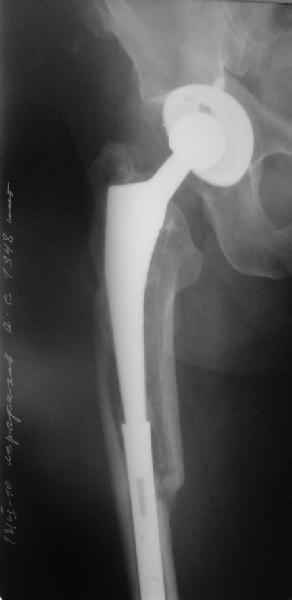

Уважаемые коллеги, в данном случае в лечении стандартного перипротезного перелома В2 Ванкуверской классификации (перелом вокруг ножки эндопртеза с потерей стабильности ножки при хорошем - не требующем пластики - качестве кости.Parvizi J, Rapuri VR, Purtill JJ, et al (2004) Treatment protocol for proximal femoral periprosthetic fractures. J Bone Joint Surg Am; 86-A Suppl 2:8-16)с успехом применён оригинальный, но малоизведанный способ лечения подобных повреждений. В результате и последующие рекомендации не могут быть стандартными. В подобных случаях, как это уже дискутировалось год назад, можно было выполнить ревизию длинной ножкой, во многом работающей как интрамедуллярный гводь + плюс кабель/серкляж в проксимальном отделе. Или, оставить имеющуюся ногу плюс длинная пластиа с кабелем/серкляжем, можно разными современными блокированными *примочками*. В таком случае при достижении консолидации пластина удаляется, тк при возникновении в будущем потребности в ревизии имеющийся дополнительный металл и без затруднит непростое вмешательство (кто пробовал, знает о чём я говорю). С длинной ногой, конечно, так же всё понятно. В данном случае мы имеем некую комбинацию, осложнённую отсутствием репозиции и фиксации в прошлом отломков вокруг ножки. Поэтому не каждый в данном случае рискнёт утверждать за счёт какого из компонентов системы - дистального либо проксимального обеспечивается стабильность. А если это и фиксация и за счёт ножки и за счёт гвоздя - каков баланс между данными компонентами в поддержании стабильности ситемы. То есть, я надеюсь, что дистального смещения ножки здесь не будет при условии сохранения как гвоздя, так и блокирующих винтов. При удалении же гвоздя возможна миграция ножки, только винтов - всей системы. Здесь же перелом (надеюсь, его не будет) блокирующих винтов может быть первым свидетельством механического неблагополучия системы... А так, помимо отличного результата этот случай так же косвенно подтверждает известную истину - Эндопротез, к сожалению, требует периодической замены. И выполняя фиксацию перипротезного перелома, а в последующем решая вопрос об удалении имплантатов, мы вынуждены думать и о функции сустава, и о том, как в будущем выполнить ревизию. Если ожидаемая продолжительность жизни пациента заставляет нас об этом думать. С уважением, Андрей

Саша, ей-Богу бы не стал. Сейчас система работает как длинная нога с дополнительным блокированием винтами (с известным допущением, конечно). И удаление половины ножки (функциональной половины), мне кажется, чревато. Мне кажется, представленная система крайне интересна дя В1 - перелом вокруг ножки, но ножка остаётся стабильной. Для В2, как в данном случае, мы не знаем, за счёт чего нога вновь стабильна - реинтеграции (не уверен), хорошего дистального и торцевого упора или комбинации факторов (склоняюсь к этому). Нарушение этого баланса может оказаться печальным для ножки. Поэтому достаточно однозначно - я бы ничего не убирал. Привет, Андрей

Уважаемый Александр Николаевич,

Как Вы знаете, мы имеем негативный опыт подобной операции (перелом ножки эндопротеза на месте соединения со штифтом), но тем не менее хотелось бы сказать следующее. На мой взгляд,выполняя такую фиксацию, мы становимся заложниками сохранения всей этой мегаконструкции на долгое время, если не на всю жизнь. Эта система работает уже как единое целое. Рефиксации ножки эндопротеза не произошло, при удалении гвоздя может развиться вторичная нестабильность, скорее всего со временем произойдут дистрофические изменения в кости за счет шунтирования нагрузки. Поэтому есть смысл отследить очень тщательно р-ты этих операций, прежде чем они войдут в повседневную практику, думаю что показания к ним будут весьма ограничены. Пару раз попробовали "пошалить", собрали бедро на бесцементной ножке у пожилых б-х дабы не утяжелять вмешательство. В одном случае - срослось и ножка получила стабильность, в другом - потребовалось реэндопротезирование, но со значительно меньшей травмой. т.к.бедро срослось.

Пока больше не было пациентов с такой своеобразной ножкой, как Zimmer CPT, которая на расстоянии 30-40 мм от дистального конца имеет диаметр всего 5-6 мм. Очевидно, при ножке с такими особенностями нужно обеспечить контакт на более проксимальном уровне, чтобы иметь больший запас усталостной прочности.